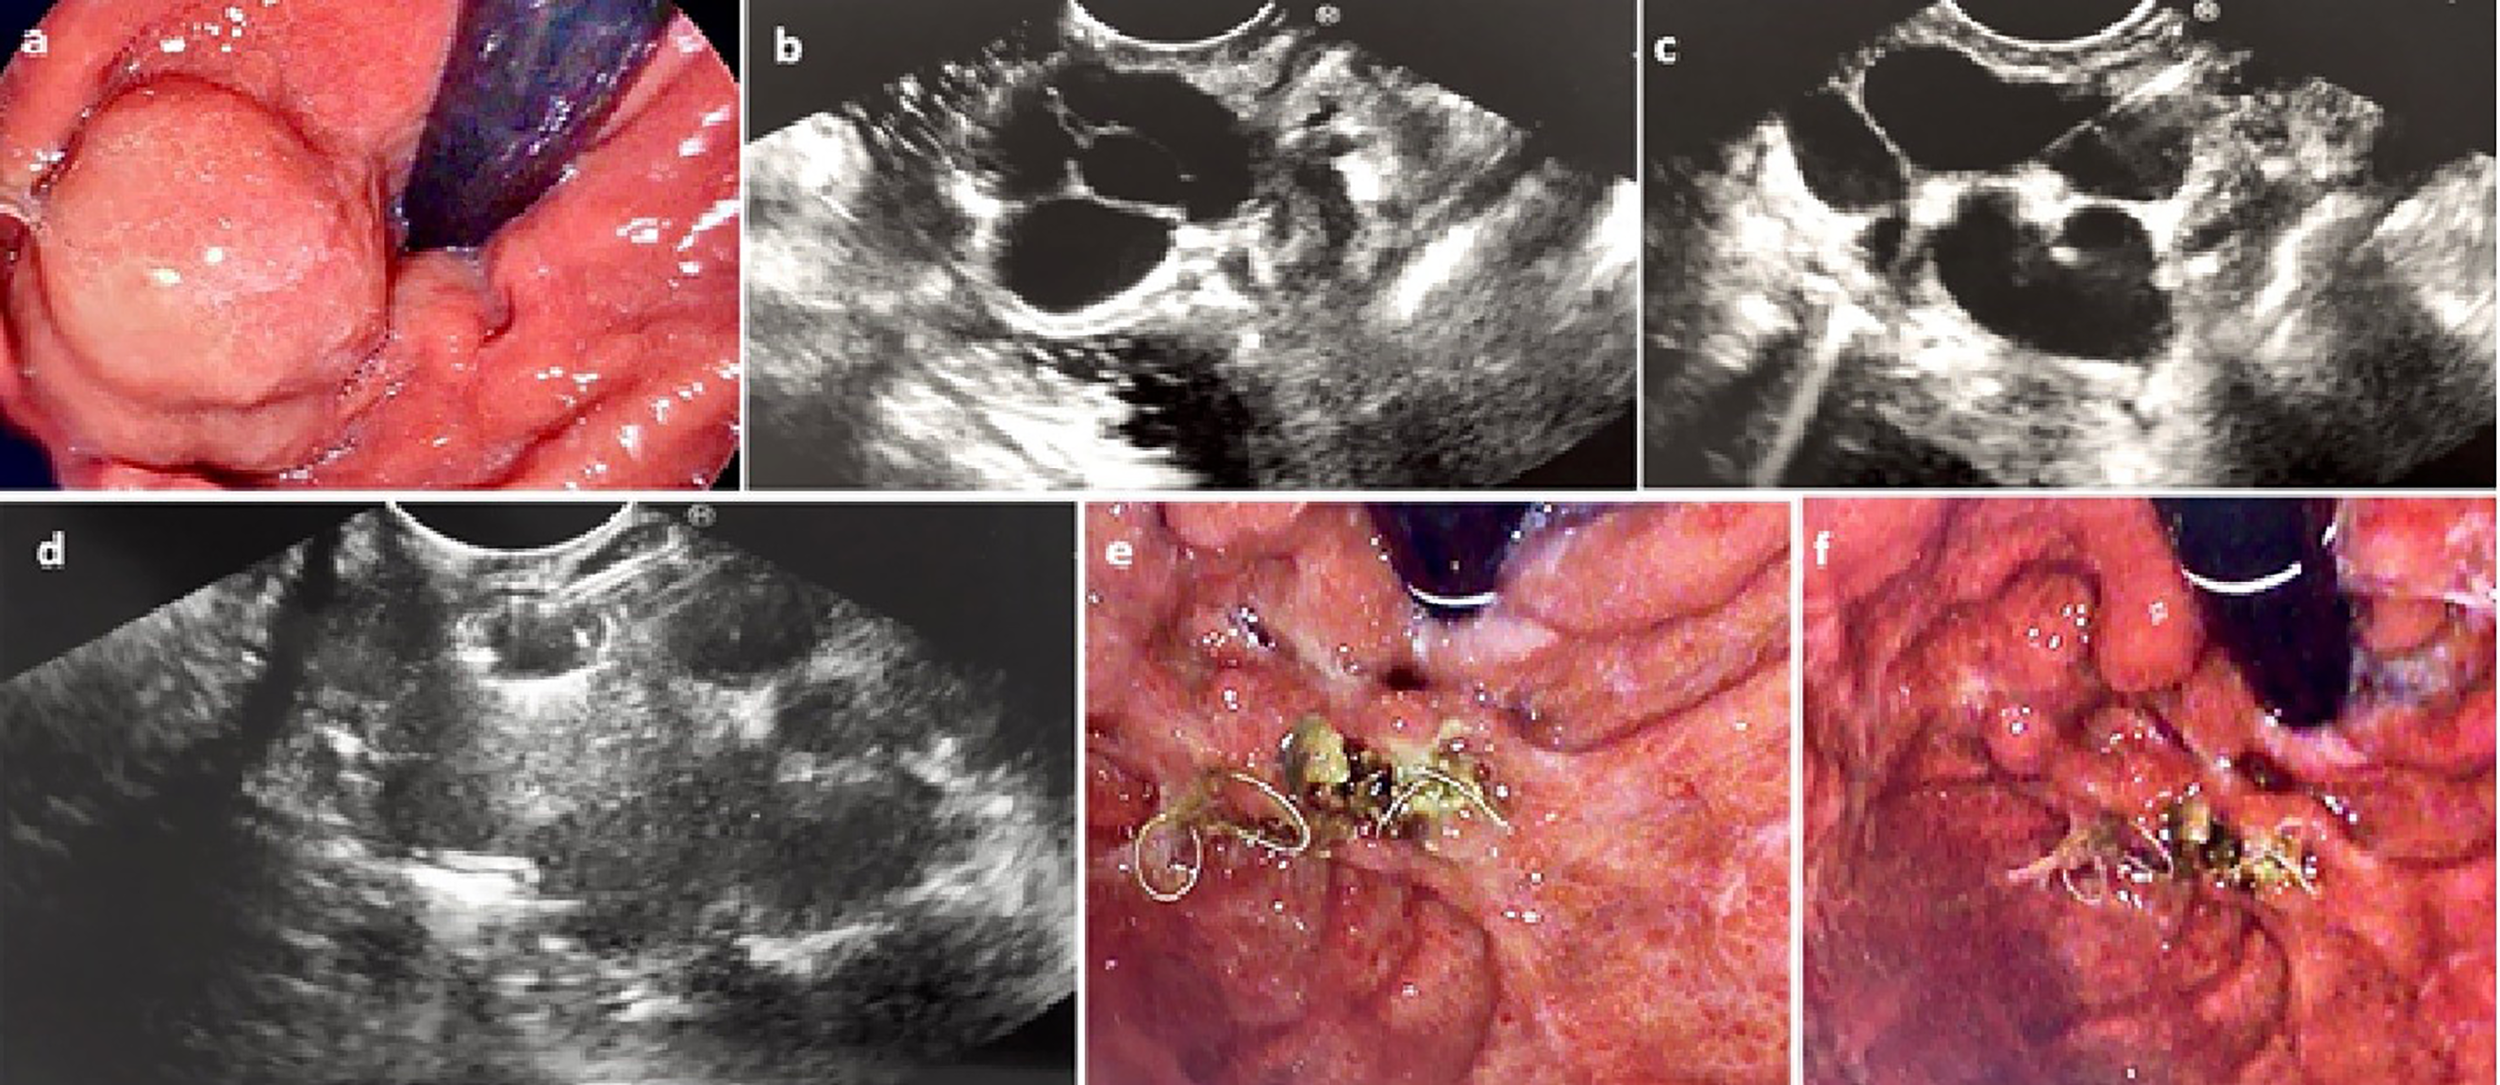

FIGURE 1

www.frontiersin.org

Figure 1 (A) Endoscopic assessment of a large IGV-1. (B) Assessment by EUS confirming large (2.6cm) intramural GV (C) The GV was punctured by 19G FNA needle (D) Coil deployed into the GV via the 19G FNA needle under direct EUS vision (E) and (F) Repeat endoscopic assessment 6 weeks later confirmed eradication of the GV with coil seen extruding from the area of the treated GV.